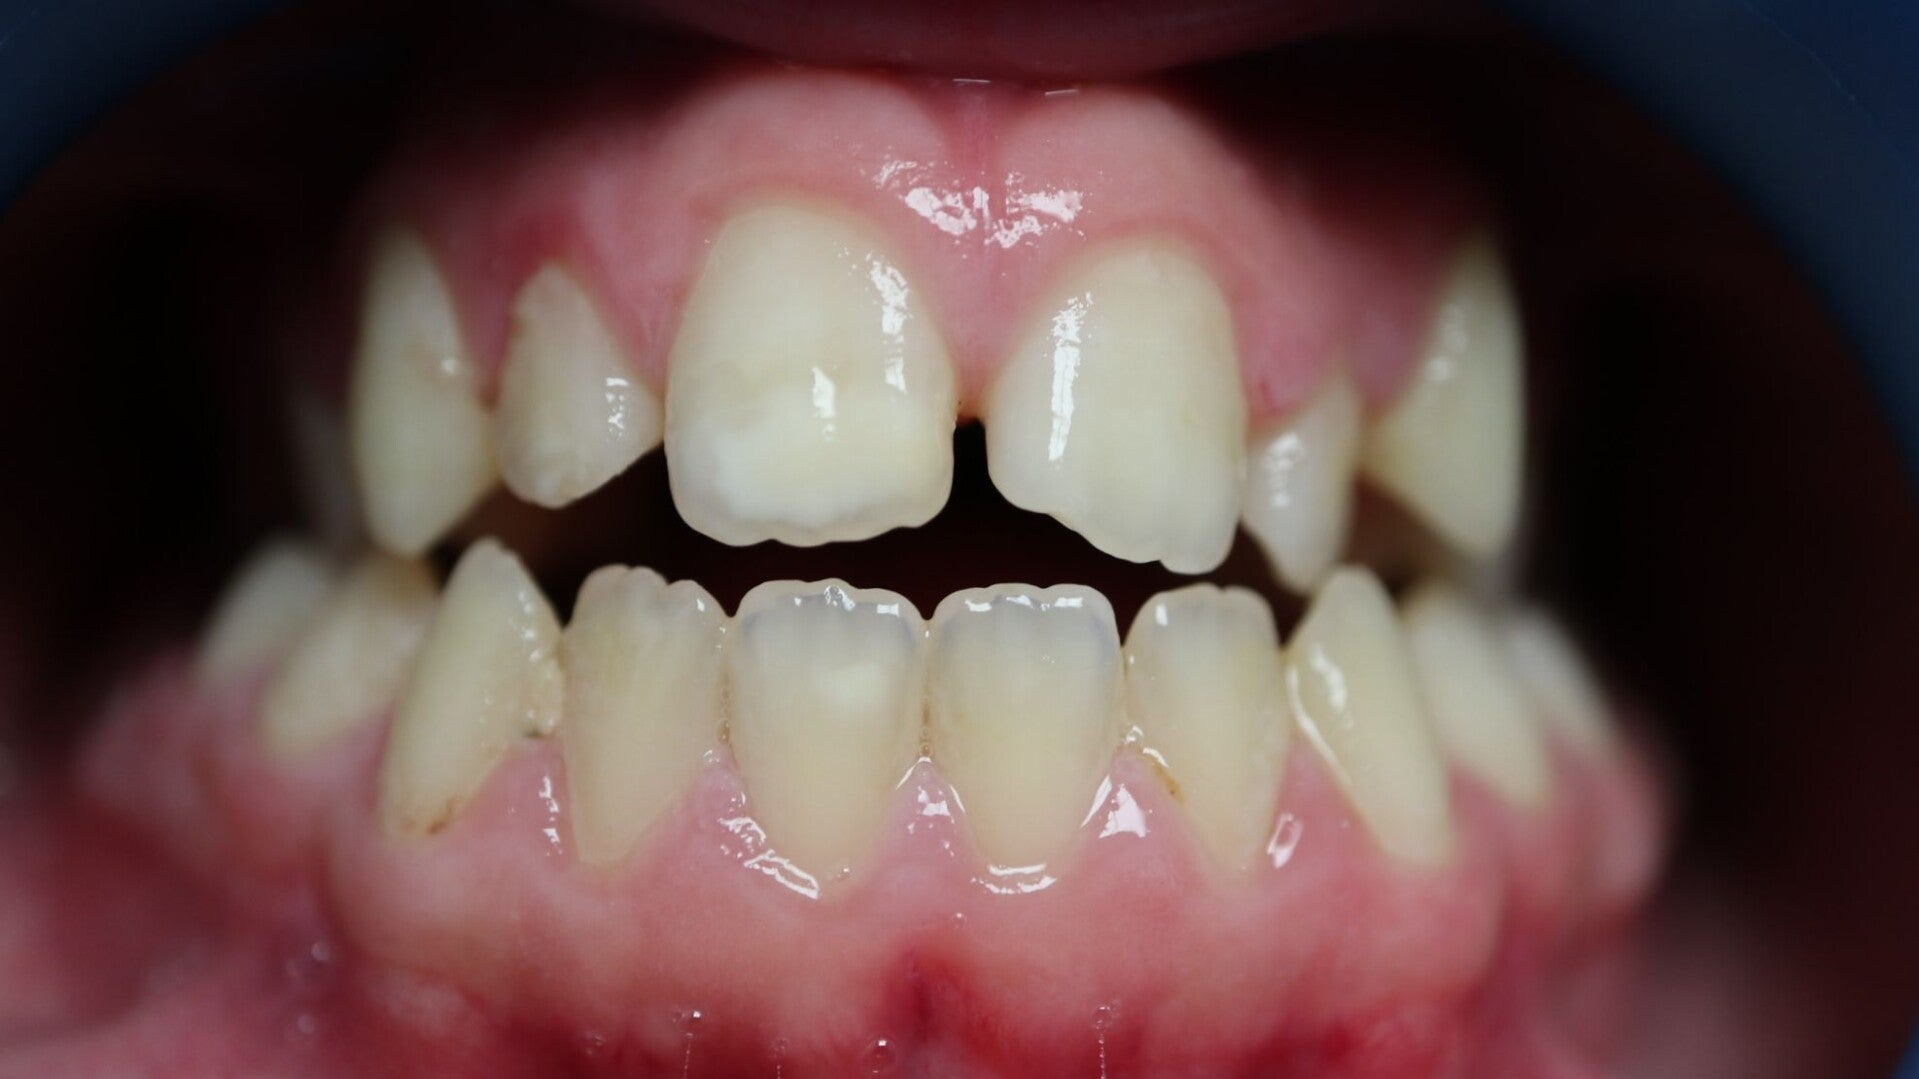

Encombrement

Les dents se chevauchent